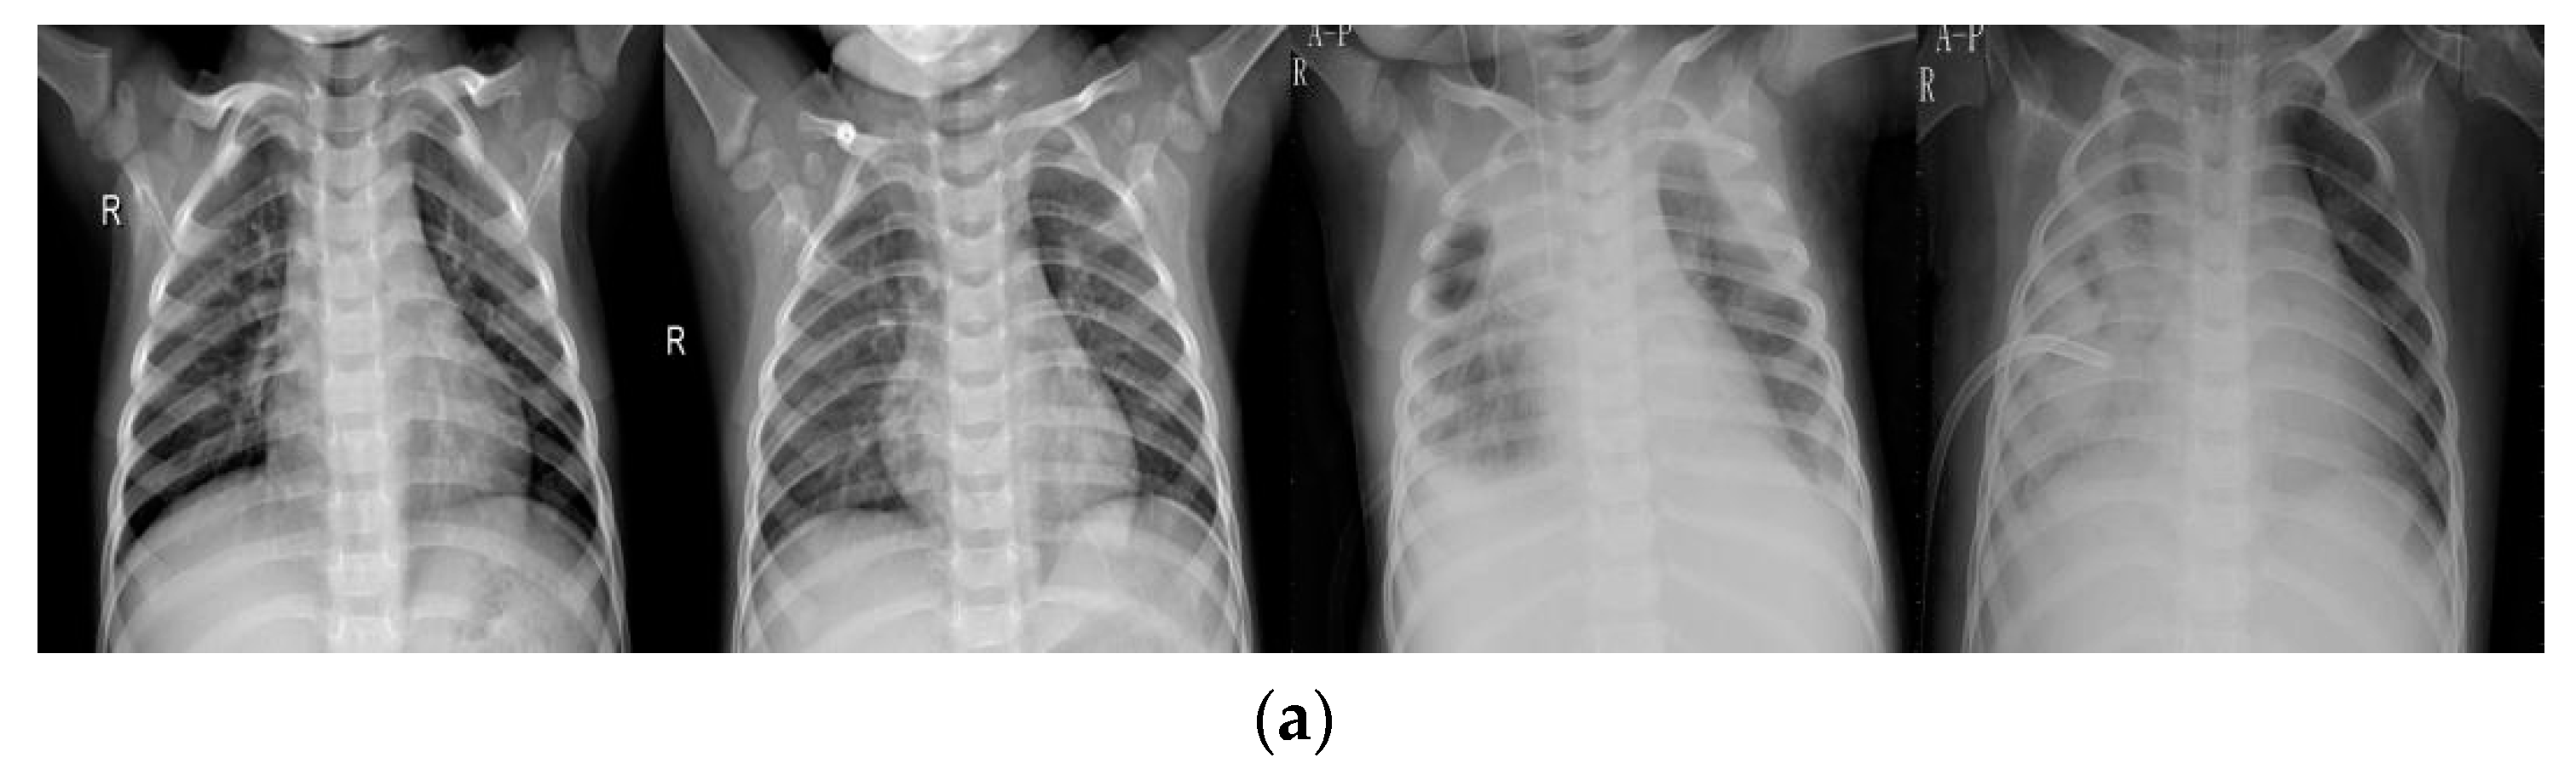

4.1. Data

4.2.1. Data Pre-Processing